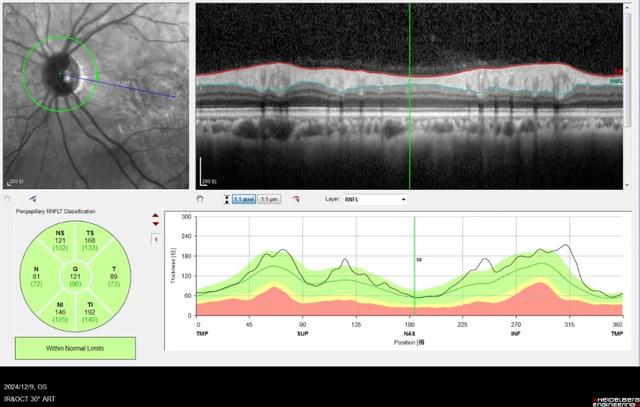

RNFL右眼

RNFL左眼

难道是球后视神经炎?但对于球后视神经炎而言,患者年龄偏大,视力及视野损伤也远较球后视神经炎来的轻,所以我认为不是。视网膜电图(ERG)也证实了我的想法,P50及N95波峰并未明显下降,提示整体视网膜及视神经功能还是可以的。mf-ERG提示双眼黄斑中央振幅明显下降,所以还是黄斑问题导致的视力下降。

既然锁定调查方向在黄斑,那接下来最应该做的就是黄斑OCT检查。在经过半个小时左右的散瞳后,OCT结果提示,双眼黄斑中心凹视网膜外层结构明显受损,椭圆体带不连续,色素上皮不规则隆起。